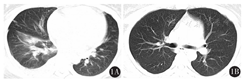

患者 女性,47岁,主因齿龈渗血2周于2013年9月11日入我院。入院后血常规示:白细胞计数5×109/L,血红蛋白60 g/L,血小板计数20×109/L;凝血酶原时间14.80 s,活化部分凝血活酶时间29.0 s,纤维蛋白原含量1.5 g/L,D二聚体6.64 mg/L;经骨髓检查,伴t(15;17),(q22;q21),PML-RARα阳性,明确诊断为急性早幼粒细胞白血病(APL)。入院查体:齿龈、皮肤有出血表现,胸骨压痛阳性,右下肺叩诊实音,右肺底呼吸音消失,考虑患者合并肺部感染。入院后立即给予维甲酸20 mg/次,每天2次诱导分化治疗,同时输注新鲜冷冻血浆、纤维蛋白原、冷沉淀纠正出凝血紊乱,输注血小板,降低出血风险,每日输注血液制品前给予地塞米松2 mg,同时给予哌拉西林钠抗感染治疗,积极完善肺部CT等相关检查。患者接受诱导分化治疗5 d后,出现刺激性干咳,伴轻度胸闷、气短。查体右肺底呼吸音消失,右肺可闻及少量湿啰音。肺部CT示:右肺下叶炎症,右侧胸腔积液(图1A)。在诱导分化治疗同时给予醋酸卡泊芬净防治真菌感染,注射用亚胺培南西司他丁钠(商品名:泰能)抗细菌治疗,并完善G试验、GM试验、T-SPOT及抗结核抗体等相关检查,结果均未见异常。患者分别于9月19日及24日出现夜间突发心悸、气短,端坐呼吸,坐卧不宁。静脉给予地塞米松10 mg后不适症状消失。期间2次复查CT均提示肺部炎症较前加重。患者经广谱强力抗感染治疗10 d,肺部症状及影像学改变进行性加重,GM试验阴性,故不支持真菌感染。经呼吸科会诊考虑感染证据不足,怀疑白血病浸润,建议通过支气管镜等相关检查明确肺部情况。但考虑肺部诊断基本明确以及出血风险,未做支气管镜检查。遂调整治疗方案,停用抗感染治疗,按分化综合征治疗,地塞米松每天6~10 mg,患者心悸、气短、面部肿胀、肺部啰音等逐渐消失,精神状况改善。10 d后复查肺部CT恢复正常(图1B)。故明确诊断为:APL伴分化综合征。

1A:右肺下叶炎症,右侧胸腔积液;1B:两肺散在炎症较前明显吸收,仅残留左肺少许炎症,未见胸腔积液,心包积液较前减少